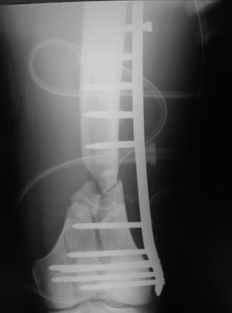

This is what we have done... As generally true for LISS look at the bone not the hardware.

There are two more srews above. The one not completely in got damaged head.

Zsolt